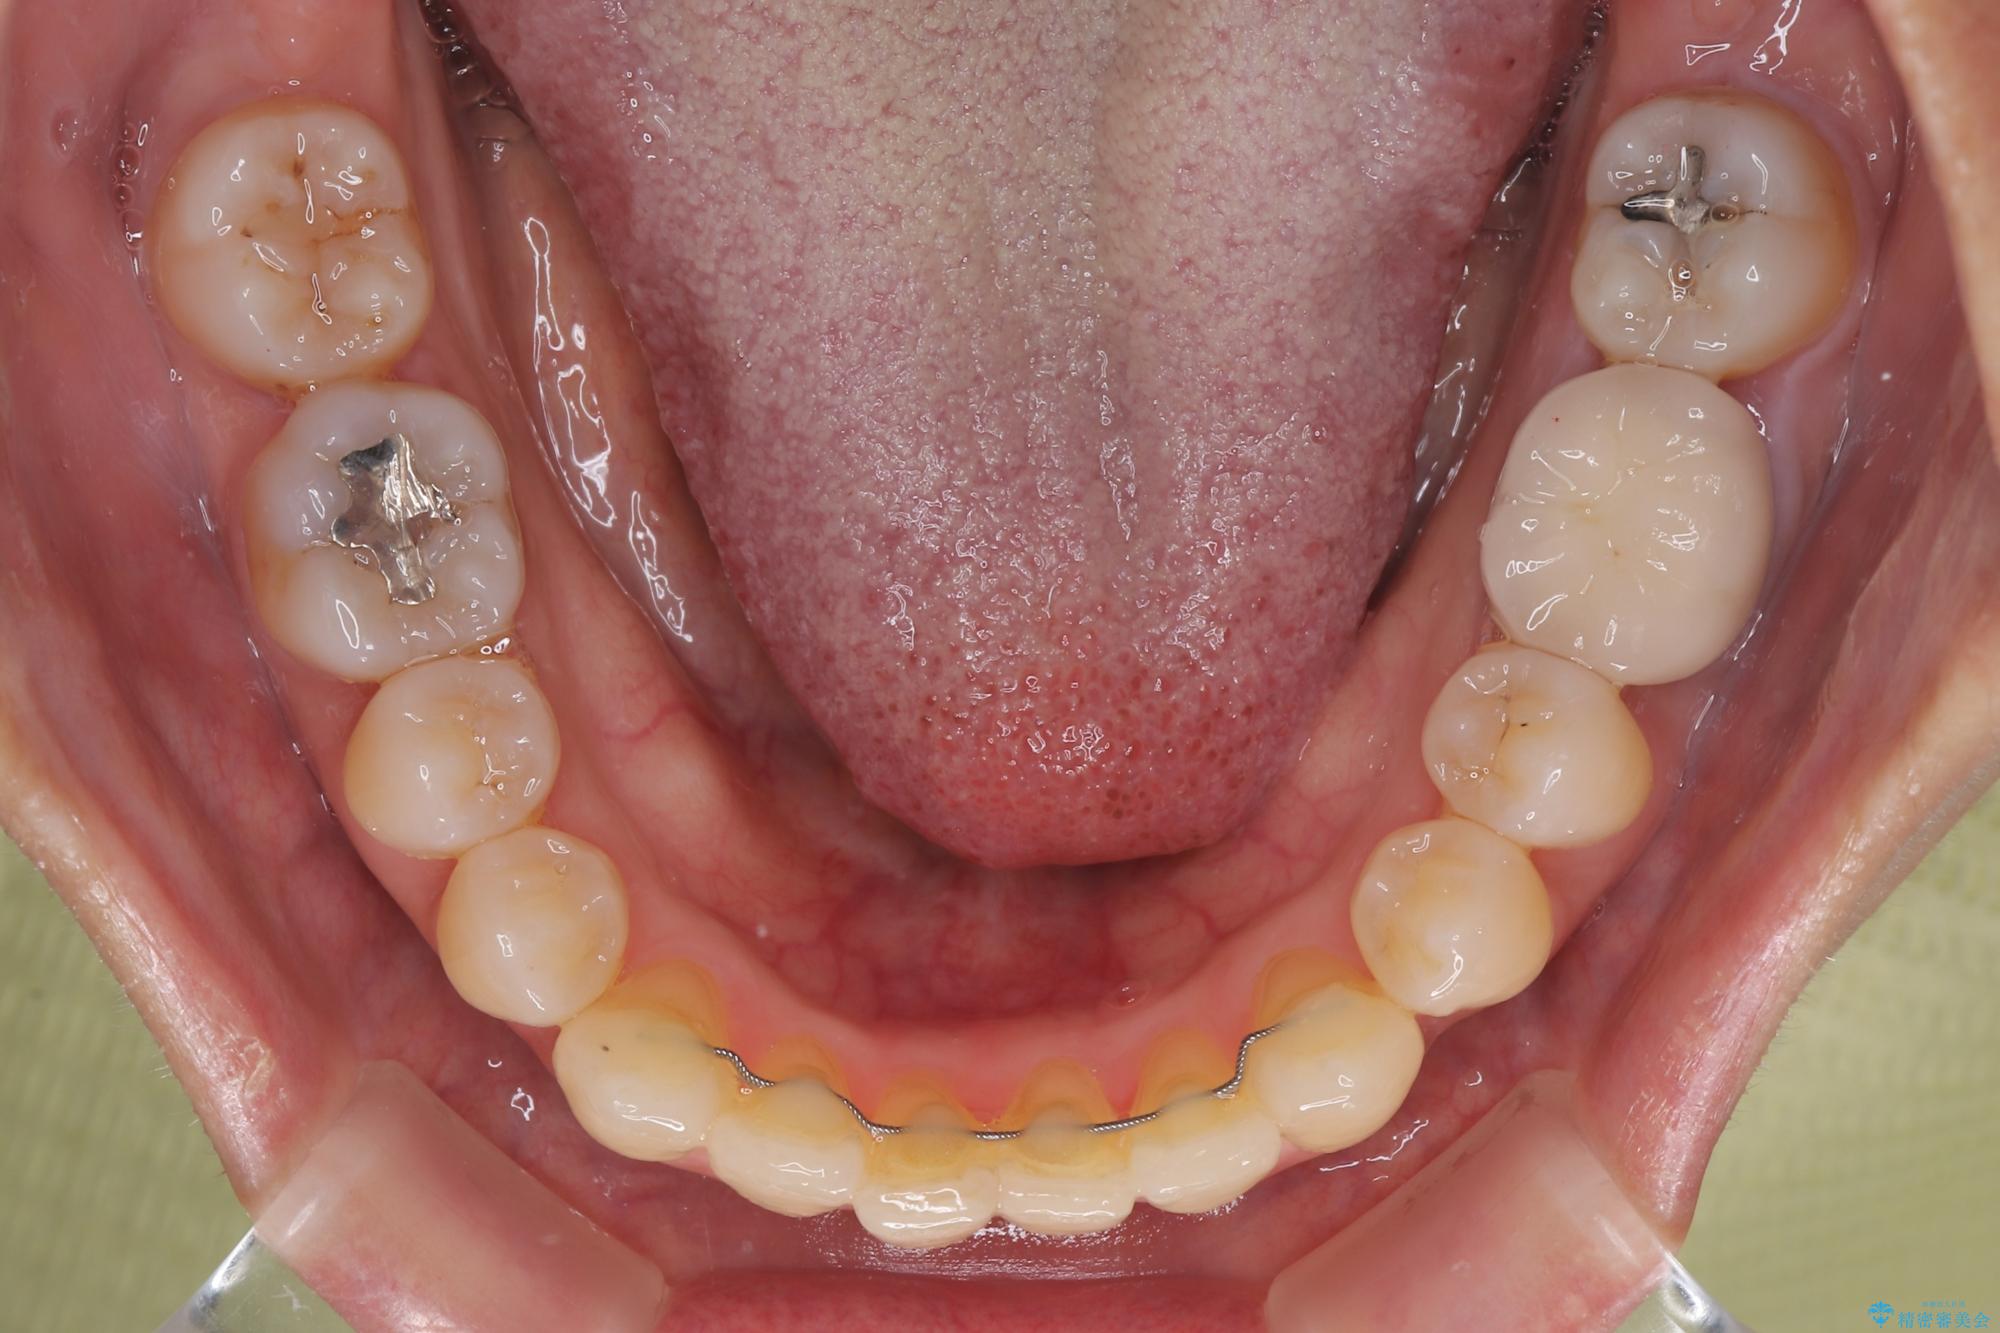

受け口と八重歯を改善 インビザライン矯正治療

- 前歯のデコボコや八重歯を治したいとのことで来院された患者様です。

受け口傾向の骨格であり、前歯はクロスバイトまたは切端咬合となっており、下顎を中心に歯列全体の後方移動を行い、IPR(歯と歯の間を削る)によってデコボコが解消するように設計し、インビザラインにより治療を行うこととしました。

受け口傾向のインビザライン矯正は比較的治療を行いやすいため、きれいに仕上げることができました。舌の突出癖が顕著であったため、改善のためのトレーニングをしっかりと行っていただきました。